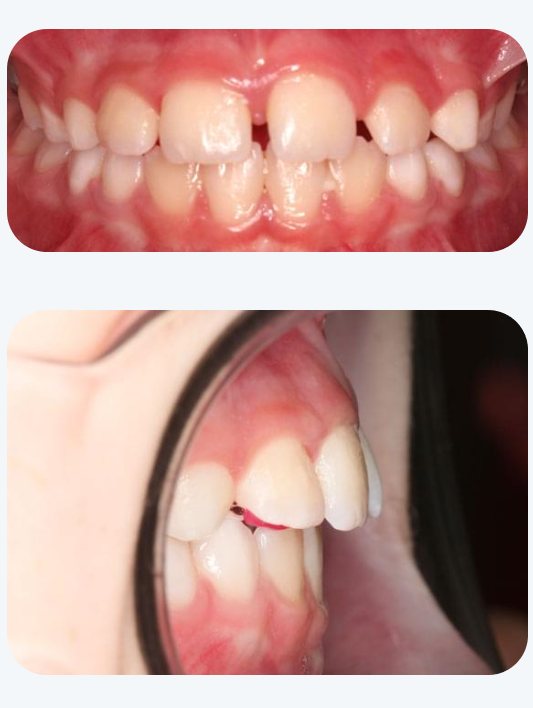

マイオブレース治療を行った症例

治療前

治療後

12歳 男子

主訴:歯並びがデコボコ

治療期間:12か月

治療経過:マイオブレース治療と筋機能療法を行った。月に1度来院していただき、お口の中やトレーニング状況を確認。

費用:40万円(税別)

※マイオブレース治療は4~5歳から開始するのがお勧めですが、上記の症例のように年齢が上がっても行える場合がございます。ご相談下さい。